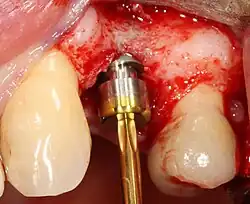

Zavedení implantátu

Většina implantátových systémů má pět základních kroků pro zavádění každého implantátu:[12]:s.214–221

- Odsazení měkkých tkání: Nad hřebenem kosti se provede řez, kterým se silnější přiléhající dáseň rozdělí zhruba na polovinu, takže konečný implantát bude mít kolem sebe silný pás tkáně. Okraje tkáně, z nichž každý se označuje jako lalok, se odsunou, aby se odkryla kost. Zákrok bez laloku je alternativní technika, při níž se pro umístění implantátu místo zvedání laloků odstraní malý úlomek tkáně (o průměru implantátu).

- Vrtání při vysoké rychlosti: Po odsazení měkké tkáně a s použitím chirurgického vodítka nebo stentu se podle potřeby umístí pilotní otvory, a to přesnými vrtáky s vysoce regulovanou rychlostí, aby se zabránilo spálení nebo tlakové nekróze kosti.

- Vrtání při nízké rychlosti: Pilotní otvor se rozšiřuje pomocí postupně se rozšiřujících vrtáků (obvykle tři až sedm po sobě jdoucích vrtacích kroků v závislosti na šířce a délce implantátu). Dbá se na to, aby nedošlo k poškození osteoblastu nebo kostních buněk přehřátím. Chladicí fyziologický roztok nebo vodní sprej udržuje nízkou teplotu.

- Umístění implantátu: Šroub implantátu je zaveden, může být buď samořezný,[29]:s.100–102 nebo se analogicky naklepe do připraveného místa . Poté se zašroubuje na místo momentovým klíčem[32] s přesným krouticím momentem, aby nedošlo k přetížení okolní kosti (přetížená kost může odumřít, což je stav zvaný osteonekróza, který může vést k tomu, že se implantát nedokáže plně integrovat nebo spojit s čelistní kostí).

- Adaptace tkáně: Dásně se přizpůsobí kolem celého implantátu a vytvoří silný pás zdravé tkáně kolem "hojícího se pillíře. Naproti tomu může být implantát pohřben, kdy je horní část implantátu uzavřena krycím šroubem a tkáň je uzavřena tak, aby jej zcela zakryla. K pozdějšímu odkrytí implantátu je pak nutný druhý zákrok.